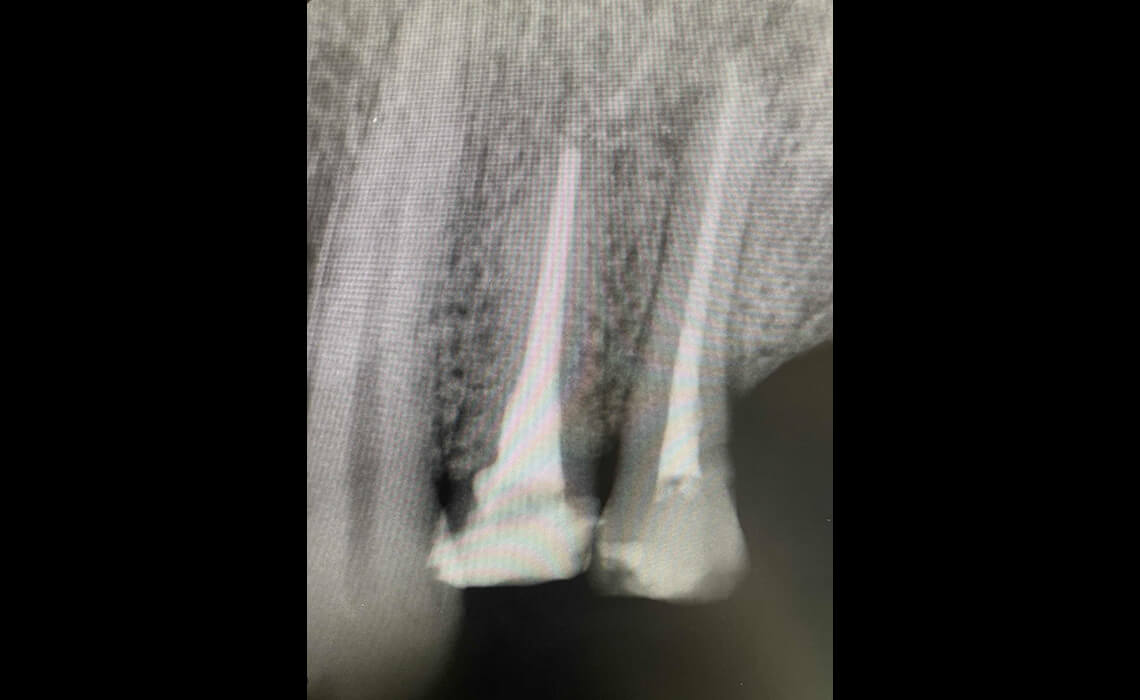

まずはカウンセリングと診査を行います。デジタルレントゲンやCTで歯の内部や根管の形を正確に把握し、治療計画を立てます。

CASE